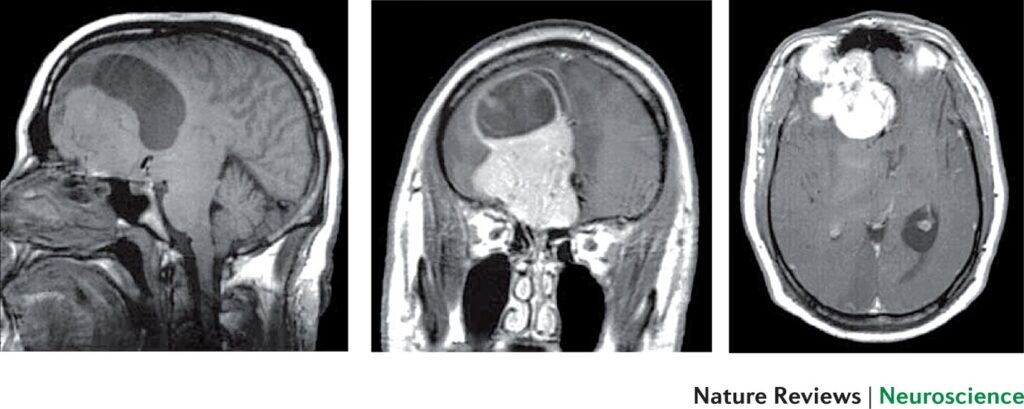

Resonancia Magnética Estructural (sMRI)

La sMRI proporciona imágenes de alta resolución de la anatomía cerebral, permitiendo a los investigadores examinar diferencias estructurales en los delincuentes. Algunos estudios han encontrado que los individuos con antecedentes de crímenes violentos pueden tener un volumen de materia gris reducido en áreas relacionadas con el control de impulsos y la regulación emocional. Esta evidencia estructural apoya la idea de que las diferencias biológicas contribuyen al comportamiento criminal.